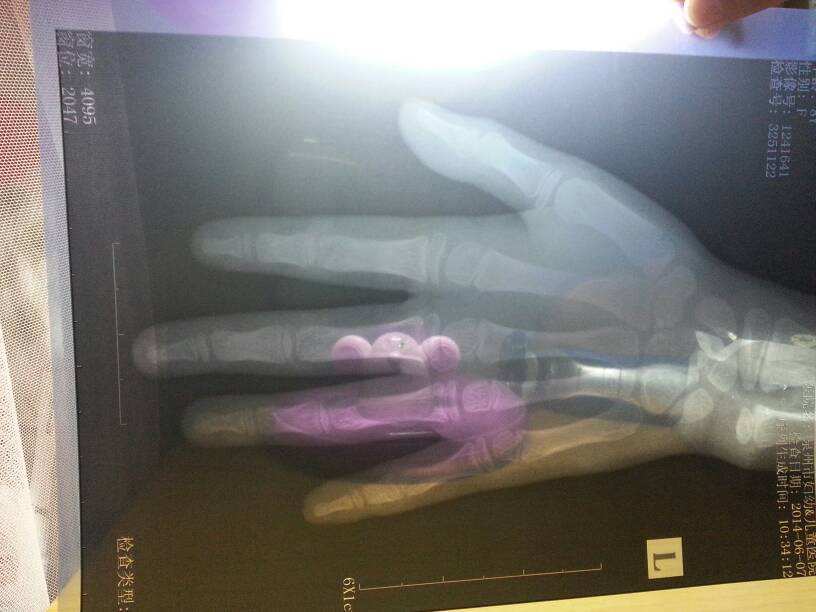

8岁10个月女孩乳房开始发育了,骨龄说9岁7个月,身高126.9,体重55.5斤,从小身高都偏低 8岁10个月女孩乳房开始发育了,骨龄说9岁7个月,身高126.9,体重55.5斤,从小身高都偏低,父母身高164;153,需要治疗吗?医生说要打针,有害处吗? 点击展开 匿名用户 2014-06-07 17:55 为您推荐: 其他回答 你好,现在小孩儿游泳都是很好的,所以体质也是很好的,你这个时候不要担心,注意给宝宝增加一下营养, 1966839485是我 2014-06-08 09:06 相关问题 请问我女儿八岁,身高133cm,体重38公斤 预测身高159cm 骨龄8 9岁左乳房开始有点发育这正常吗 女孩性早熟,乳房有发育,现在年龄是7岁10个月,骨龄检查是8周岁,要不要打针 女孩9岁,身高体重骨龄子宫都正常,连续5天乳头胀痛变红变硬,检查卵巢偏大,激素很高,应怎么控制住激素?